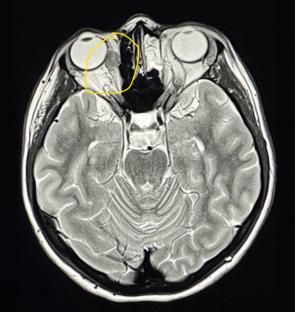

But a chest X-ray found the true cause â stage four melanoma, which had spread throughout her body, including seven tumours in her brain, and more than 20 tumours in each of her lungs.

“They found seven brain tumours, at least 18 in my liver, and at least 20 in each lung, plus two beside my heart, and tumours in my spine and adrenal gland.

Kaylee soon started immunotherapy, as well as radiation to treat the tumours in her brain.